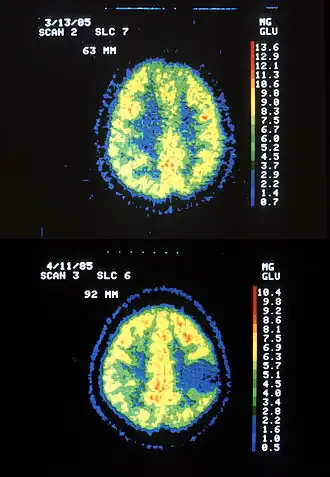

Astrocytome de bas grade dans le mésencéphale (flèche) en séquence T1 à l'IRM, vue sagittale Scanner IRM d'un patient atteint d'un astrocytome montrant l'évolution sur 7 ans.

Scanner IRM d'un patient atteint d'un astrocytome montrant l'évolution sur 7 ans.